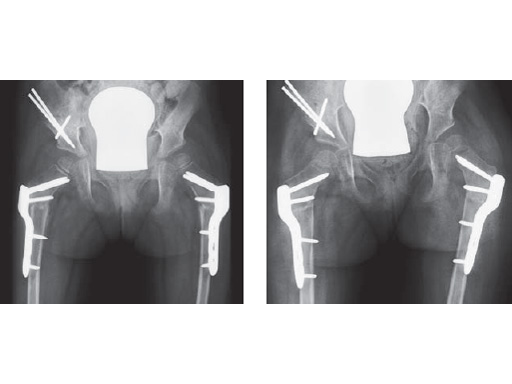

4-years-old female, CP, good walker

Fig. 1

Hip instability due to severe hip dysplasia and severe coxa valga

Fig. 2

Abduction shows an acceptable containment; a 35 varus OT bilateral in combination of a triple OT on the right is planned

Fig. 1-2

Postoperative x-ray with planned correction